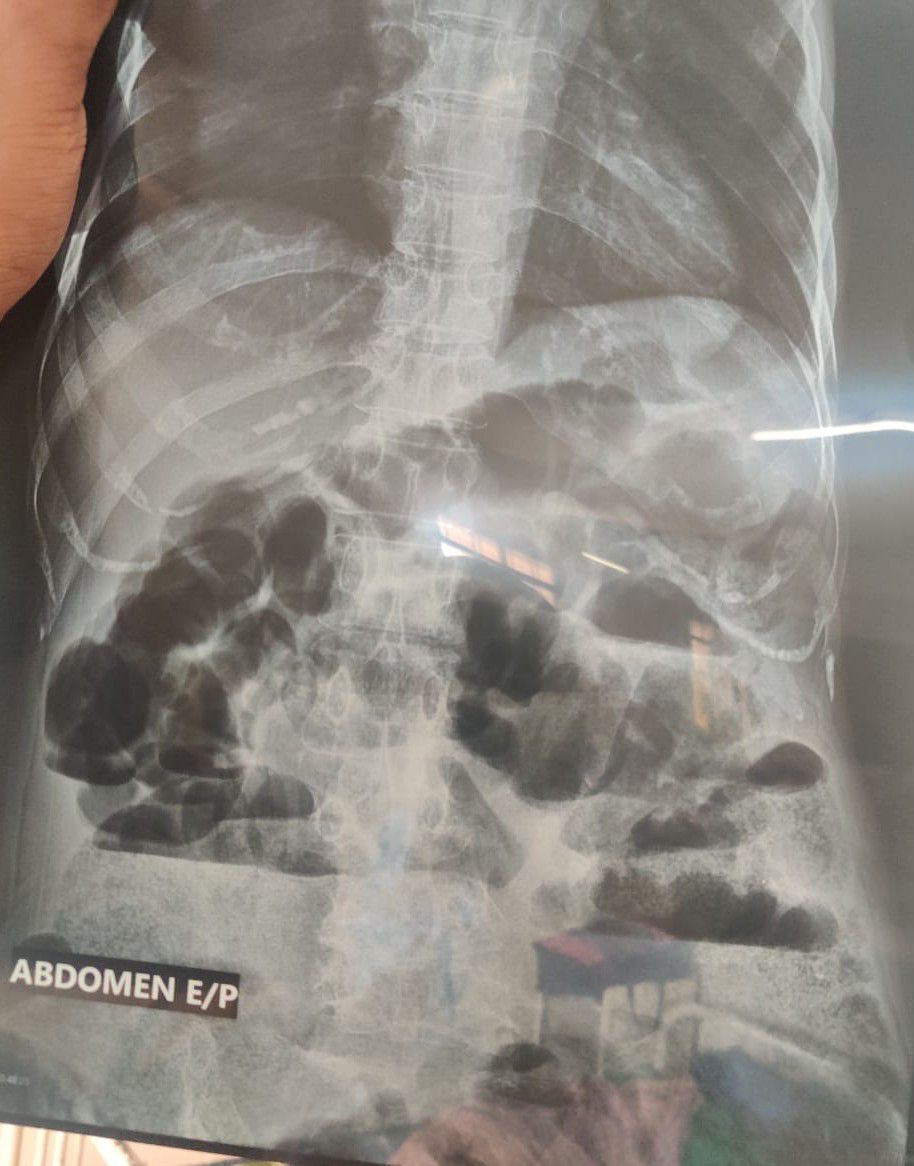

A case of Intestinal obstruction due to abdominal tuberculosis.

Radiology

Tuberculosis

Intestinalobstruction